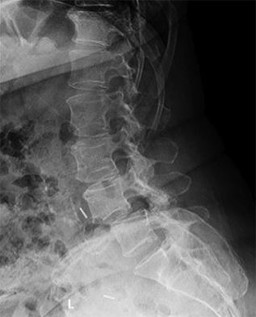

A 45-year-old male with a 20-year history of ankylosing spondylitis presents to the emergency department after a low-energy trip and fall at home. He complains of new-onset, severe lower cervical neck pain. Neurologic examination is unremarkable.

Standard AP, lateral, and odontoid plain radiographs are interpreted as normal. What is the most appropriate next step in management?